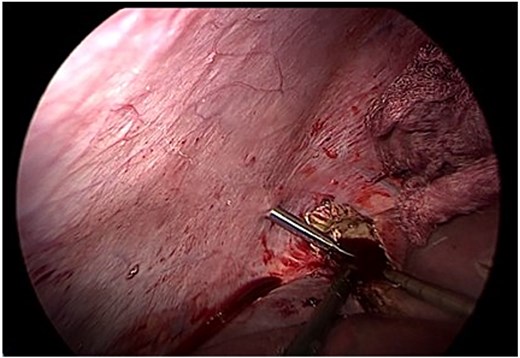

The laparoscopic procedure was performed using four trocars. The operative field was protected with gauze soaked in 17.7% hypertonic saline to reduce the risk of peritoneal dissemination. The cyst was punctured, and a scolicidal agent (17.7% hypertonic saline) was instilled into the cavity and retained in situ for 15 minutes before aspiration. A secondary suction device was used to minimize leakage (Fig. 2).

Intraoperative view of controlled puncture and aspiration of cyst contents. Gauze soaked in 17.7% hypertonic saline protects the operative field to prevent spillage.